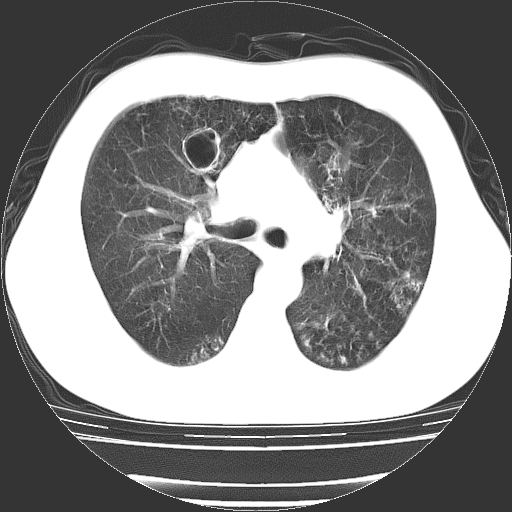

以下是引用zyx168在2006-12-4 15:30:00的发言:[br]经典!支气管肺囊肿并感染。

以下是引用dyqct在2006-12-4 17:11:00的发言:[br]典型的囊状支扩合并感染。

以下是引用liaoqiang在2006-12-4 16:12:00的发言:[br]局部肺叶内可见扩张的支气管壁,考虑为支扩。部份囊样影内有小液平和肺内散布斑片征影、小结节及纤维灶,提示支扩伴感染,且由于局部呈现有树芽征感染以结核可能性大。

以下是引用zhoucan076在2006-12-4 16:48:00的发言:[br]囊状支扩合并感染